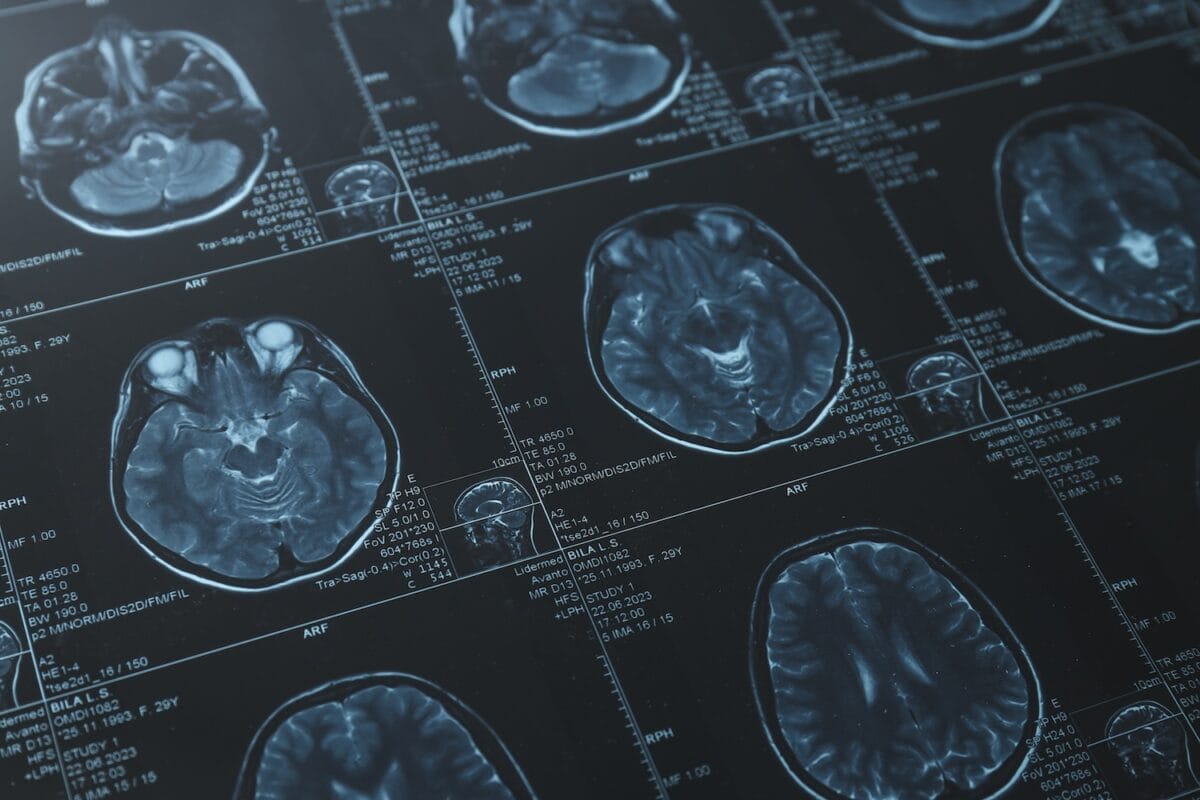

- Diagnostic testing, such as CT scans or MRIs

A TBI occurs when a sudden blow, jolt, or penetrating injury disrupts normal brain function. These injuries often happen during serious accidents, and they can range from mild concussions to life-altering brain damage.

Medical professionals typically classify traumatic brain injuries into several categories: